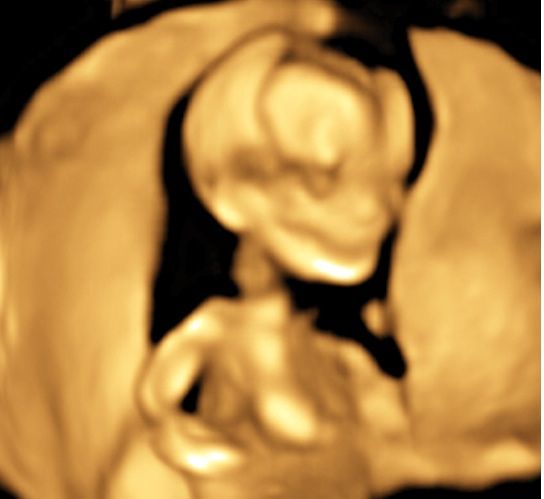

Realizamos las ecografías de viabilidad del embarazo, genética, morfológica, de bienestar fetal, ecocardiografías fetales, así como procedimientos invasivos como biopsia de vellosidades coriales y amniocentesis.